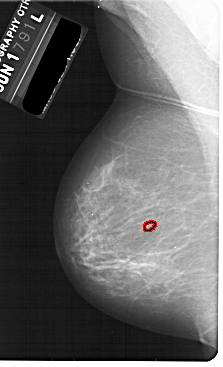

A_1870_1.LEFT_CC

LEFT_CC LINES 5491 PIXELS_PER_LINE 3256 BITS_PER_PIXEL 12 RESOLUTION 43.5 OVERLAY

FILE: A_1870_1.LEFT_CC.OVERLAY

TOTAL_ABNORMALITIES 1

ABNORMALITY 1

LESION_TYPE CALCIFICATION TYPE PLEOMORPHIC DISTRIBUTION CLUSTERED

ASSESSMENT 4

SUBTLETY 1

PATHOLOGY BENIGN

TOTAL_OUTLINES 1

BOUNDARY